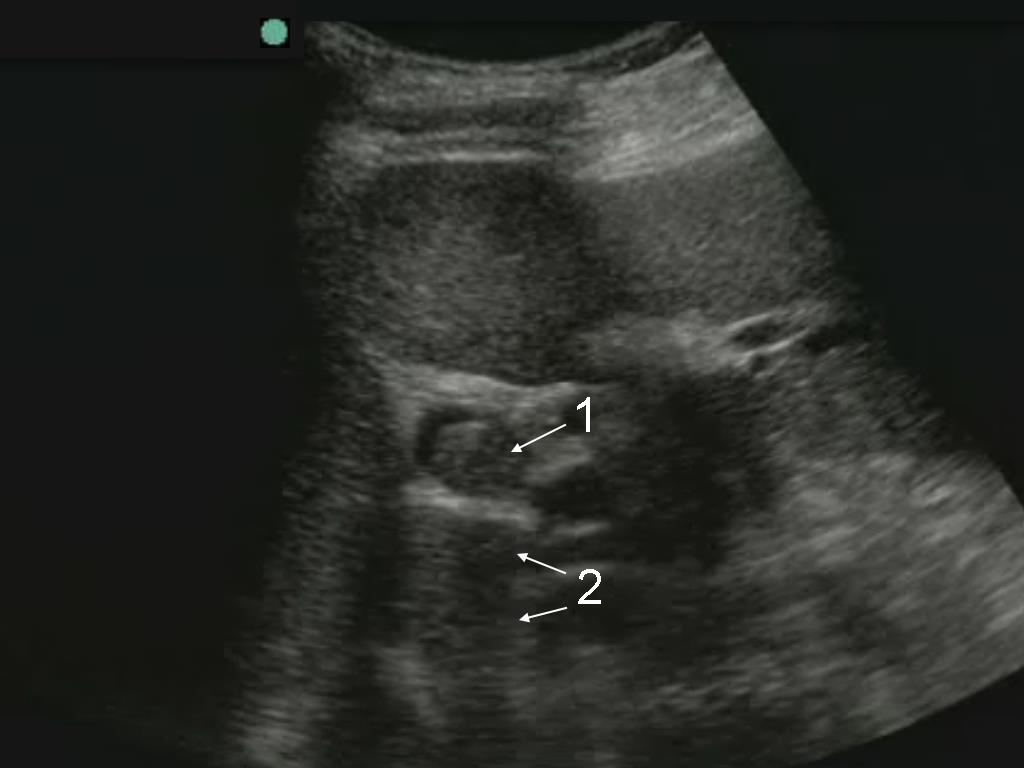

Gallbladder Common Bile Duct Stone (CBD) – Transverse Image

1. Common Bile Duct (CBD) Stone

2. Shadowing from Stone